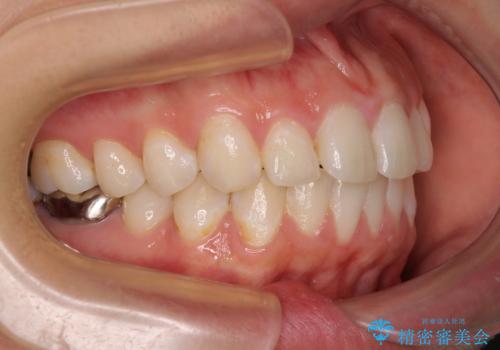

奥歯の虫歯は事前に矯正治療用の仮歯に置き換えて矯正治療を行い、装置除去後にセラミッククラウンにて補綴治療を行うこととしました。

通常は上下左右の第一小臼歯4本を抜歯することになりますが、左側下顎の第二小臼歯は既に根管治療をされており、予後が良くないとのことでこの歯を抜歯し、ワイヤー装置にて矯正治療を行うこととしました。

第二小臼歯抜歯はイレギュラーな治療手段であり、治療期間が延びる傾向にありますが、予定よりも早い2年間で終えることができました。